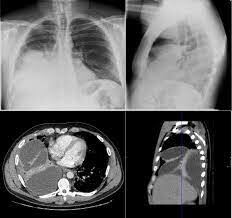

• 1989 - TC en Tórax

1989 - TC en Tórax